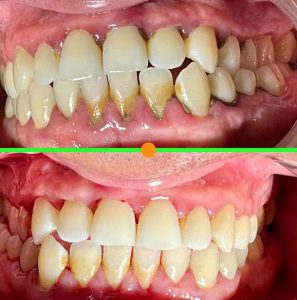

Tratamientos Ortodoncia Blanqueamiento dental Zoom Contacto 72 2795 9597 Marcar Ahora Envia whatsapp Visita nuestro facebook